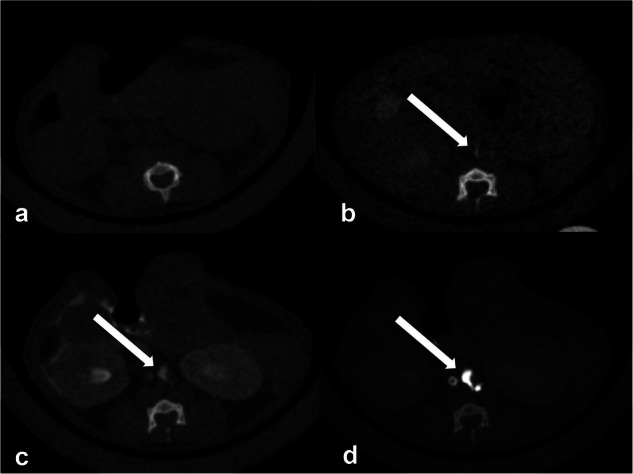

Methods: Twelve female BALB/c mice were injected with 35 μL of iodinated contrast medium (iomeprol 350 mgI/mL) into the mesenteric (mesenteric group) or popliteal (popliteal group) lymph nodes. CT images were acquired before injection and 1 min, 3 min, 5 min, 10 min, and 15 min after injection using a micro-CT scanner. Contrast ratios (CRs) were measured at the cisterna chyli and three levels of the TD (diaphragm, carina, and venous angle). Two experienced radiologists qualitatively assessed images as good, fair, or poor.

Results: The mesenteric group had significantly higher mean (± standard deviation) CRs than the popliteal group for all examined regions at 1 min after injection: cisterna chyli (14.01 ± 4.77 versus 1.47 ± 1.21, p < 0.001), diaphragm (7.28 ± 2.50 versus 0.85 ± 0.61, p = 0.0011), carina (10.33 ± 3.42 versus 0.44 ± 0.40, p < 0.001), and venous angle (6.26 ± 2.02 versus 0.79 ± 0.75, p < 0.001). For the TD between the cisterna chyli and the diaphragm, 6/6 mice in the mesenteric group showed strong enhancement, whereas 5/6 mice in the popliteal group showed minimal or no enhancement. The visual scores of the mesenteric group were significantly higher than those of the popliteal group for all the evaluated regions (p = 0.002).